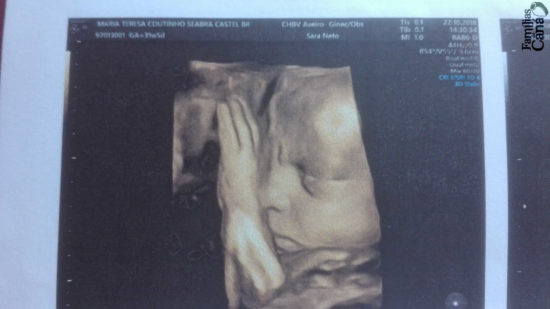

Os teus olhos viram-me em embrião… (Sl 139/138)

As palavras do salmo descem devagarinho da cabeça ao coração, enquanto acaricio o ventre, contornando um pezinho espetado aqui e ali, sempre em movimento. Admiro o salmista, que recebeu de Deus a inspiração deste poema de amor, desvendando os segredos da Criação. Há milénios atrás, sem o recurso a ecografias, o salmista já tinha consciência de que o corpo do bebé dentro da mãe não se confunde com o corpo da mãe nem lhe pertence, antes lhe pede ajuda, com absoluta confiança, para se desenvolver feliz. Pertencer, pertence apenas ao seu Criador, como diz outro salmo: